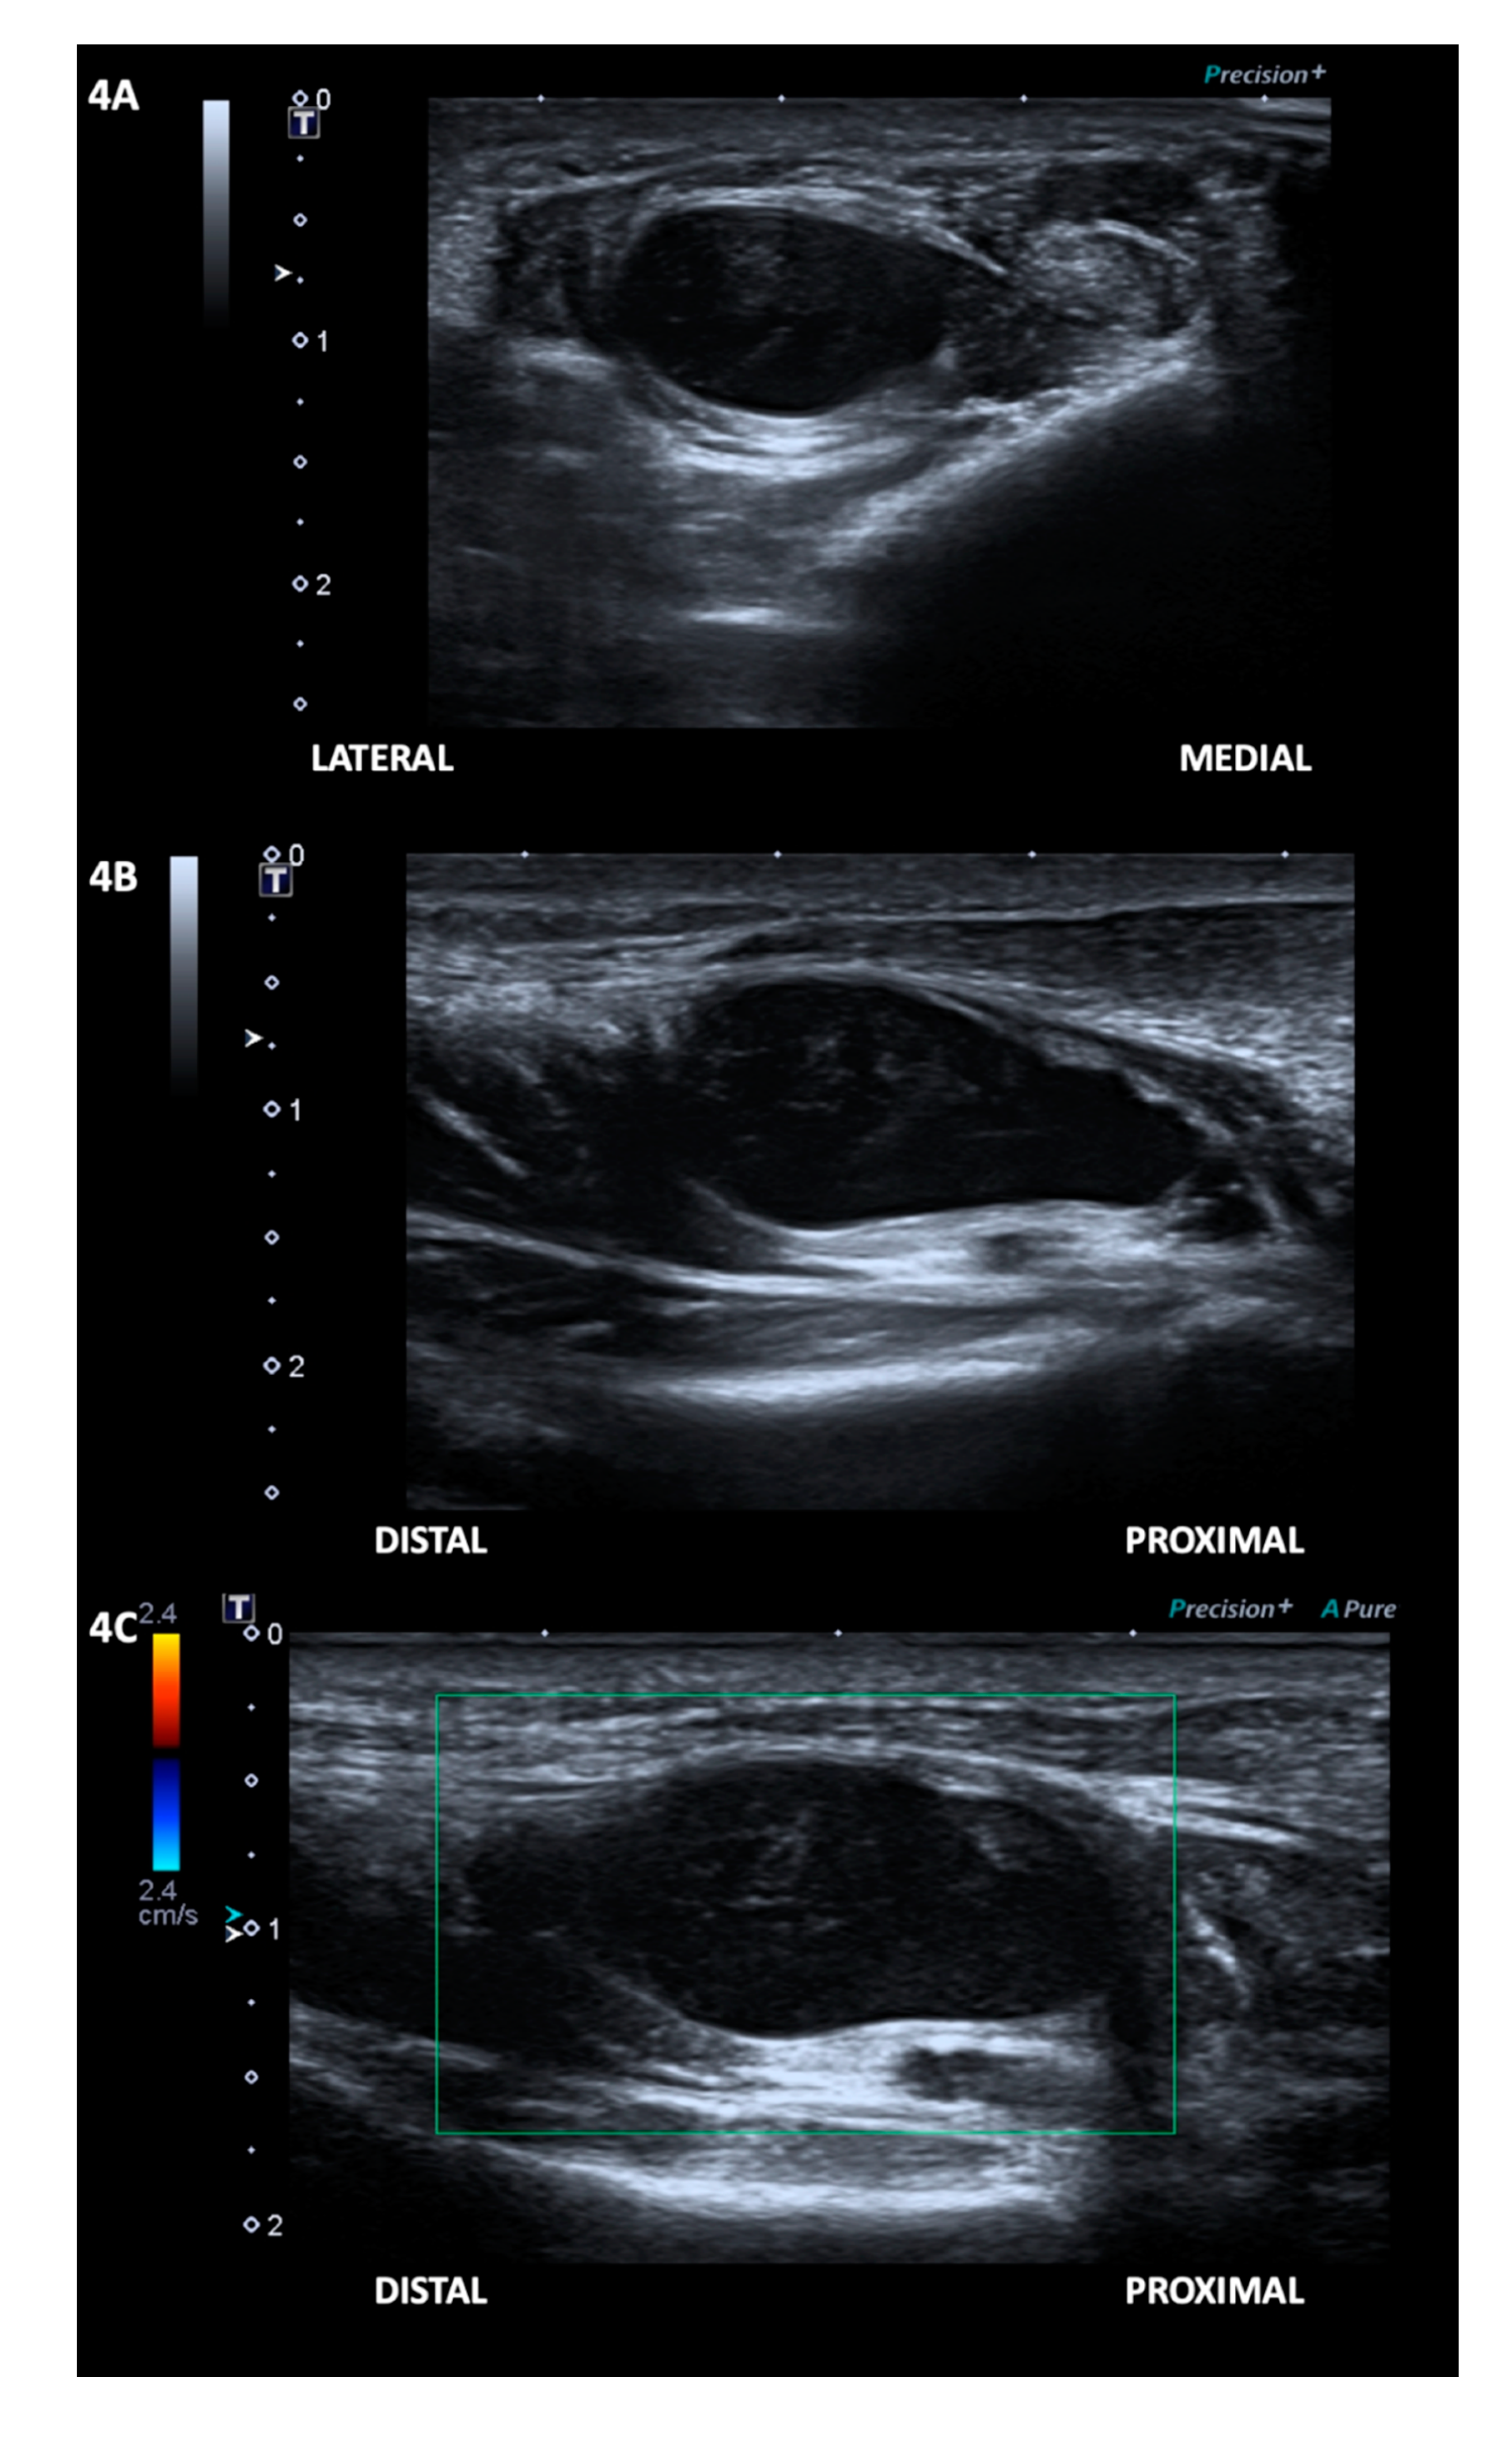

2. Case Presentation